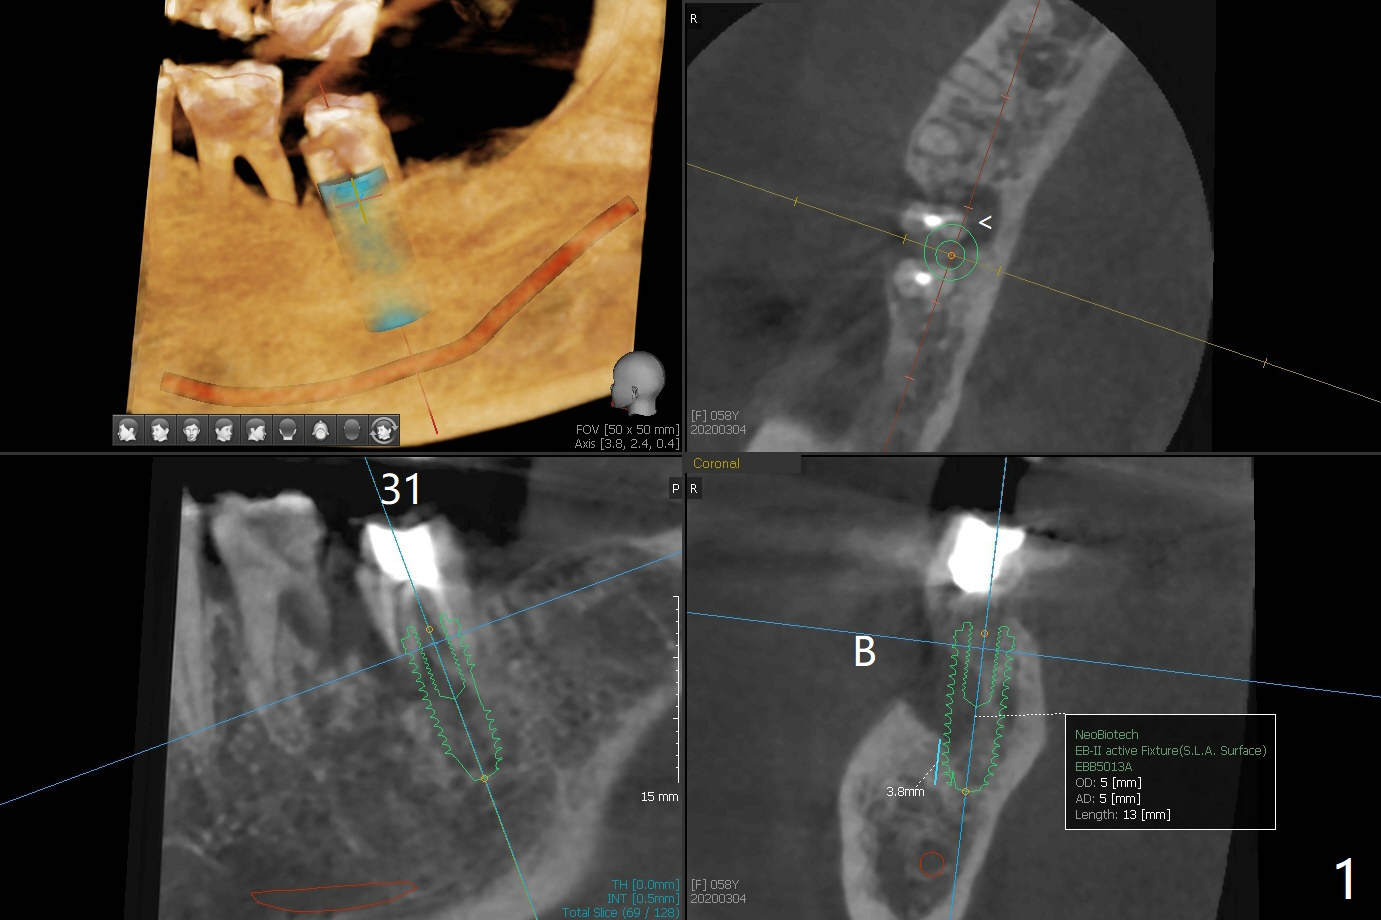

A 58-year-old woman has infection after RCT at #31, as related to mesial root fracture (Fig.1 <).  Although primary stability should be able to be achieved (3.8 mm in the native bone), a 5x13 mm immediate implant may be too long for mouth opening with guide.  Augma may be indicated.   Use a condenser to push bone cement apical.   But the inventor does not agree.  Take preop photos to show the buccal fistula.   Prepare IBS kit for free hand placement and GEM21S.  Without immediate implant, the buccal plate will collapse.